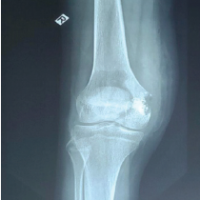

A 15-year-old male presented to clinic complaining of 3 months of worsening right knee pain. Imaging revealed a bone lesion within the medial femoral condyle, and open biopsy revealed chondroblastoma (Fig. 1).